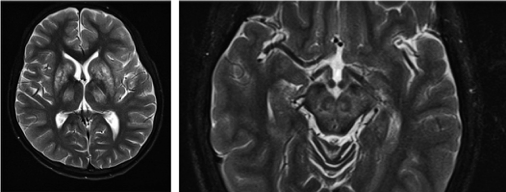

- Brain MRI

Bilateral abnormal signal in the striatum and thalamus in Wilson’s disease (left) and ‘face of the giant panda’ (right) on T2 weighted MRI sequences in Wilson’s disease.